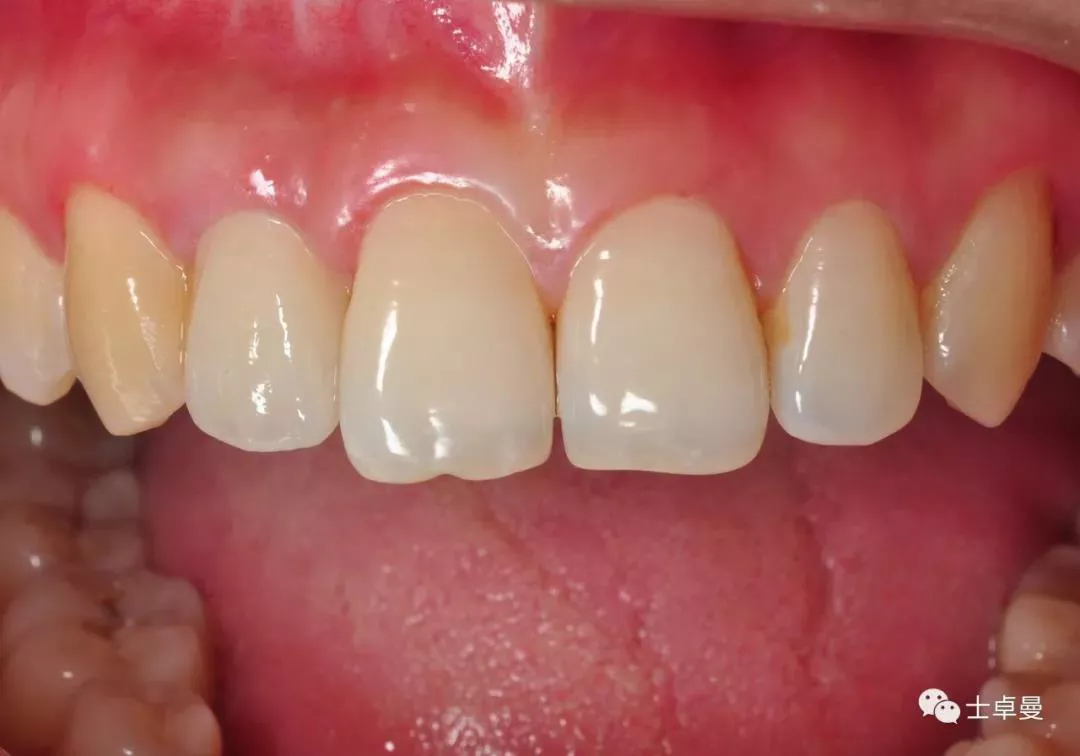

术前口内照

断根舌侧劈裂至龈下3mm-4mm

·        唇侧龈缘曲线完好,与邻牙协调,牙龈质地健康,无炎症,薄龈型;

·        残根不松,叩诊不适;

·        11、21之间有约1mm-1.5mm缝隙;